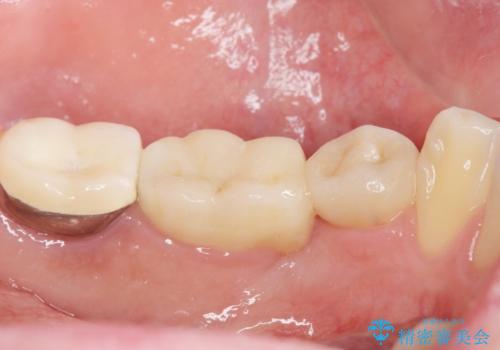

セラミッククラウンにより、抜歯した部分のスペースを閉じ歯並びを整えました。

矯正装置を用いることなくセラミッククラウンにより歯並びを整えスペースを閉じることができ、大変ご満足頂けました。

クラウンの種類:オールセラミッククラウン スタンダード